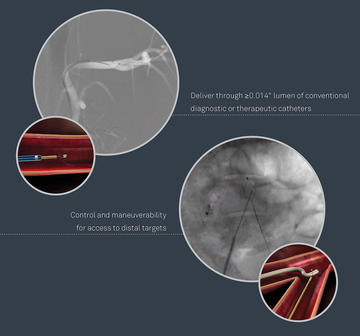

The MICRO Elite Snare is intended for use in the retrieval and manipulation of atraumatic foreign bodies located in the coronary and peripheral cardiovascular system and the extra-cranial neurovascular anatomy. This is the only 0.014'' compatible guidewire-based snare.

Micro Elite Snare

Micro Elite Snare: a 0.014" compatible guidewire-based snare